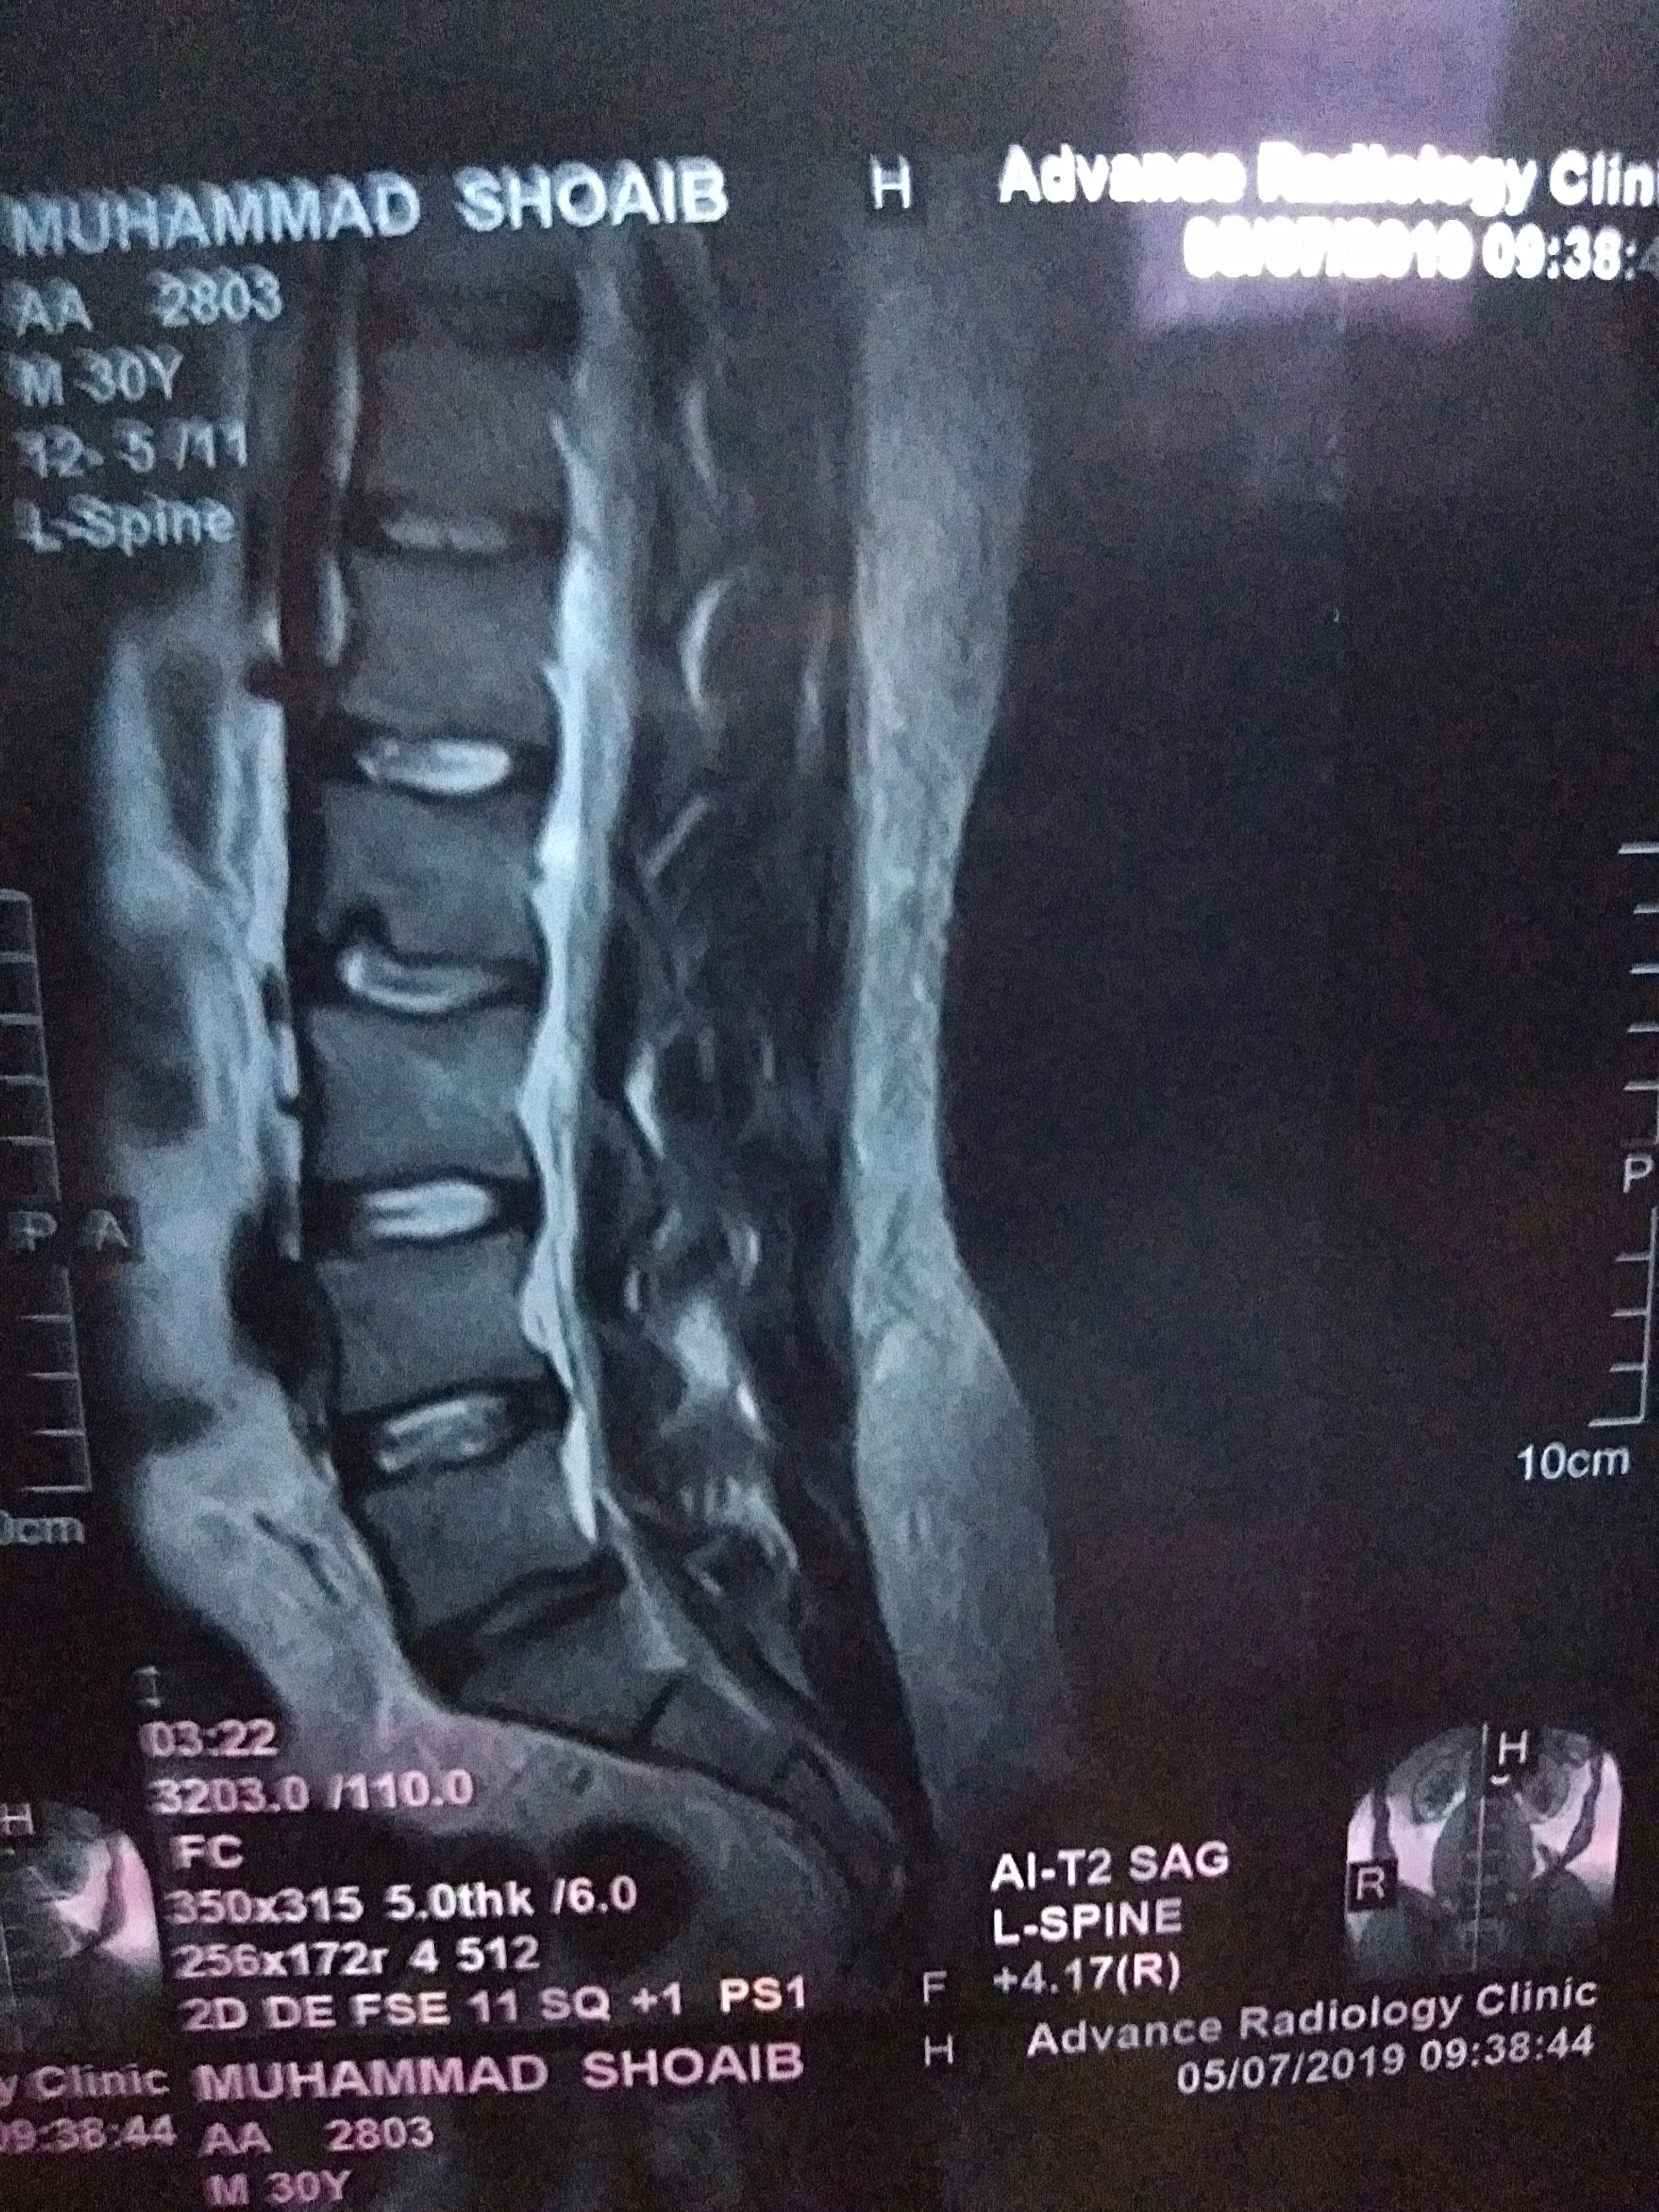

On 30nth April I was suffering from sever back and leg pain, after a day the pain was gone by taking some pain killers.. but day after tomorrow my thighs heel became numb .. And after MRI of lumbar sacral region and as per neurosurgeon Diogenes I have an problem in l5 s1 which disc is suggested me a surgery in first visit.. and a injection called epidural steroid injection ... I am scared from surgery and from this injection by reading of its risks from different internet channels ...